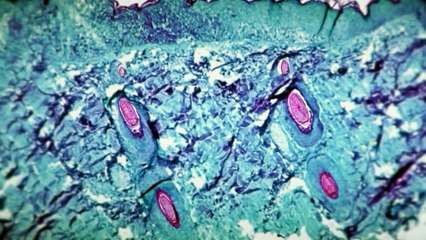

Francia abre centros de vacunación contra la viruela del mono para evitar más contagios